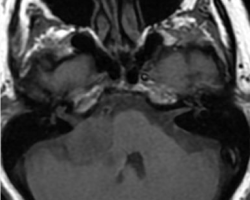

Un homme de 55 ans, n’ayant aucun antécédent personnel est envoyé pour réaliser une IRM par son ORL pour exploration d’acouphènes associés à une hypoacousie droite ainsi que des vertiges et une paralysie faciale périphérique droite d’apparition récente.